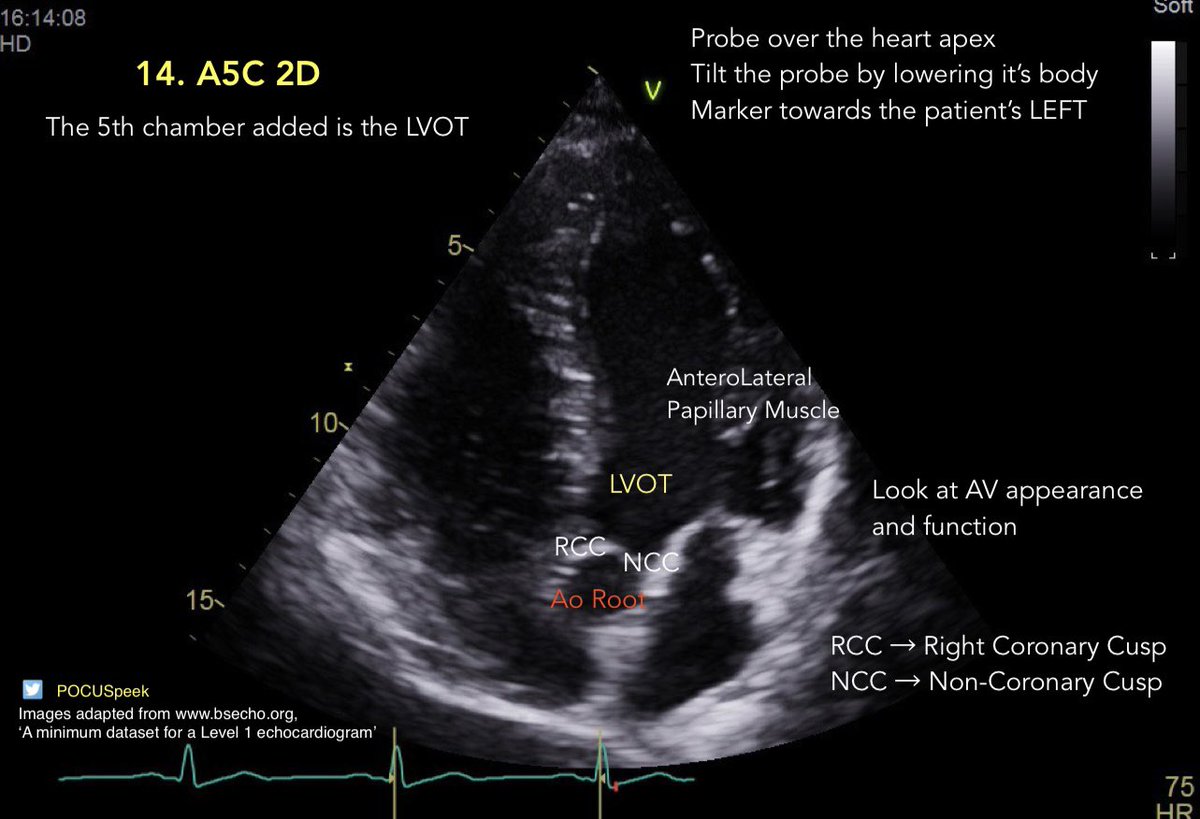

Some annotated #firstecho #POCUS main views 👇🏻 3/3

POCUSpeek's tweet image. Some annotated #firstecho #POCUS main views 👇🏻 3/3